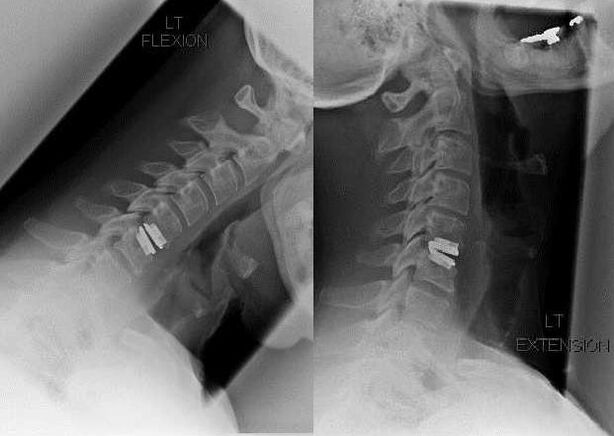

As indicacións para a intervención cirúrxica inclúen a ineficacia do tratamento conservador e as complicacións da osteocondrose cervical, por exemplo, a mielopatía discoxénica, a síndrome da arteria vertebral e a síndrome radicular. Para aliviar a carga sobre a medula espiñal, os vasos sanguíneos e as raíces da columna, realízanse as seguintes operacións:

- laminectomía;

- laminotomía;

- foraminotomía;

- facetectomía;

- Discectomía.

Durante a cirurxía, pódense extirpar fragmentos óseos e ligamentos e os discos intervertebrais poden ser eliminados total ou parcialmente. Para pequenas protuberancias de hernia, adoita realizarse a vaporización con láser do núcleo do disco.

Despois da eliminación das estruturas vertebrales, adoita ser necesaria a estabilización dos segmentos de movemento da columna vertebral mediante a fusión da columna vertebral ou a instalación de autoinjertos óseos e de pel.